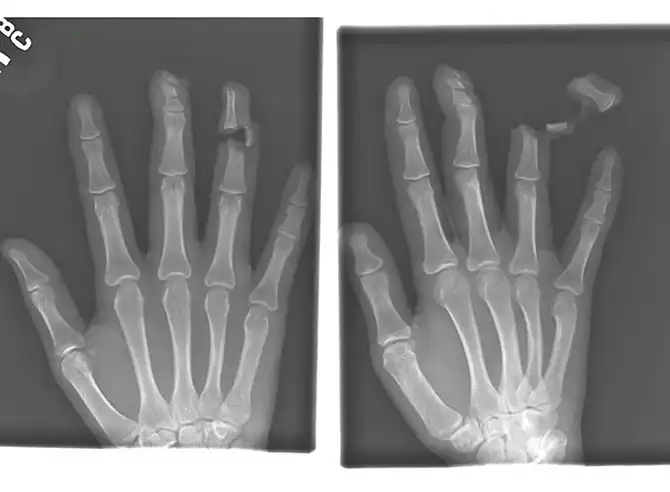

Гвоздь в костях указательного и среднего пальцев взрослого мужчины.

Разорванный палец пациента, который подрался с человеком, вооруженным ножом.